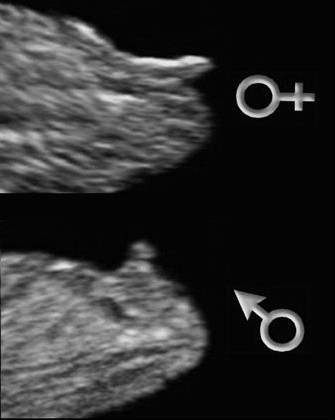

La Calculatrice du Sexe du Bébé fille ou garçon se base sur le calendrier chinois de grossesse qui affirme pouvoir prédire si le bébé sera un garçon ou une fille en se basant sur lâge de la maman et la date de la conception du bébéPour cela si vous voulez utiliser la Calculatrice de Garçon ou Fille il vous suffit simplement. Cest cette après midi les filles que jai mon écho à 1630. Le moyen le plus fiable de connaître le sexe du bébé est léchographieLa première échographie se déroule au cours du troisième mois de grossesse entre la 11e et la 13e semaines daménorrhéeDans certains cas le sexe du bébé peut-être annoncé lors de ce premier examen explique le Dr Philippe Mironneau gynécologue et.

Ce calendrier chinois a plus de 700 ans et il est très utilisé en Chine surtout avant la conception pour connaître en fonction du sexe désiré et de lâge de la. Au cours dune de ces échographies les parents qui le souhaitent peuvent découvrir si leur futur bébé est une fille ou un garçon. Pour ma part mon grand père le faisait sur ses vaches pour savoir si elles allaient donner un mâle ou une femelle et ne sest jamais trompé.